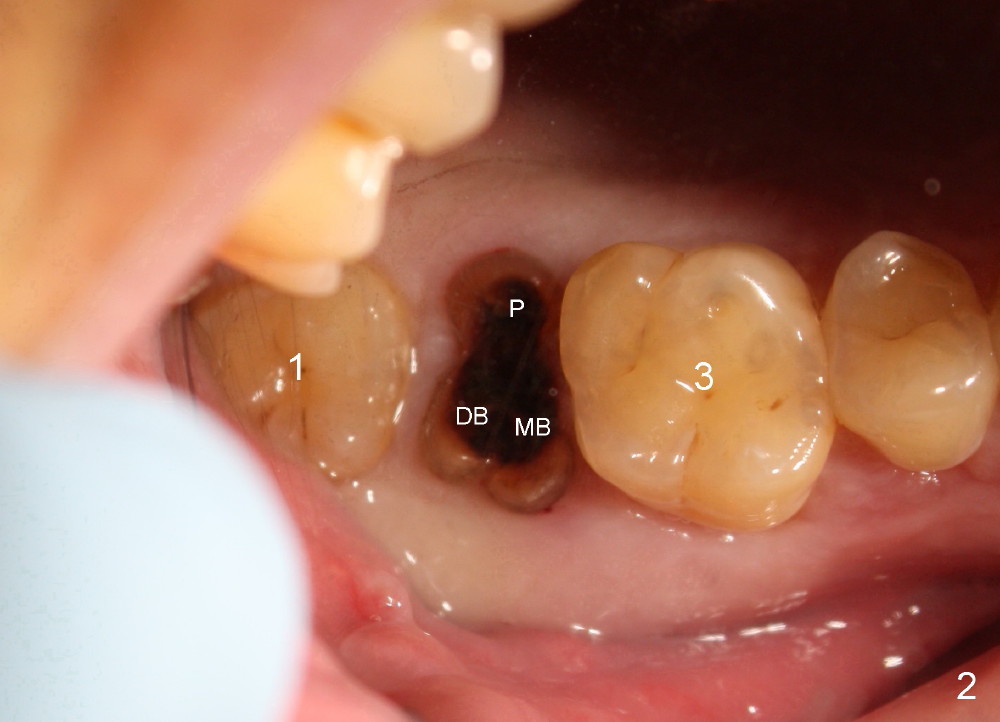

A 42-year-old man is afraid of dentistry. Residual roots of #2 remain untreated for at least 2.5 years (Fig.1). Both the mesiodistal space and the height are limited and unfavorable to restoration (Fig.2,3). Finally he agrees to have treatment, since the tooth #15 is worn so much that it is sensitive to mastication. When the tooth #2 is extracted, the socket is triangular without septum (Fig.4); the bottom of the socket is flat and easy for osteotomy. A 5x17 mm tap has obtained stability once it is placed ~ 14 mm deep (Fig.5). A 5x14 mm implant is placed with insertion torque > 60 Ncm (Fig.6 I), followed by placement of 4x3 mm abutment (A).

To prevent the narrow spaces from getting worse during osteointegration, an immediate provisional is to be fabricated. There is not enough occlusal clearance when the abutment is reduced ~1.5 mm. The abutment is removed; the implant is placed ~ 1 mm deeper with primary stability. Then the occlusal clearance is sufficient; the provisional is made. Mixture of autogenous bone, allograft and Osteogen is placed in the remaining buccal and lingual sockets (Fig.7 *). The provisional is temporarily cemented (Fig.8 P), which keeps the bone graft in place.